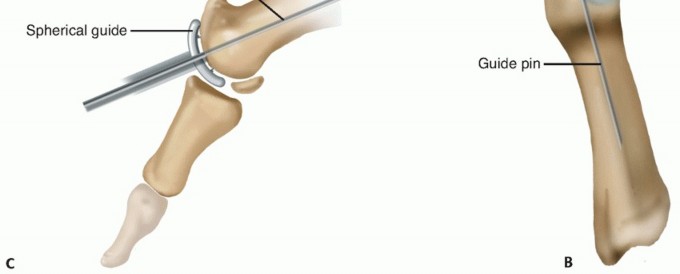

- TECH FIG 2 • A. A tap is used within the first metatarsal head, stopping at the etched line on the driver when flush with the plantar articular surface. B. A taper post screw is placed to the etched line when flush with the joint surface. C. Intraoperative use of tap to etched line using inferior aspect as reference point. D. Intraoperative screw placement. E. The screw is stopped when the etched line is flush with the remaining joint surface using the inferior aspect as the reference point. F. Screw can be advanced past etched line if bony decompression desired. Each one quarter-turn past the line equals 1 mm additional joint decompression. (continued)

- TECH FIG 2 • (continued) G-I. Space can be created within joint by decompression of metatarsal side. Example depicts 2 mm additional decompression from previous joint line by advancement of screw by half turn past etched line, followed by surface reaming preparation and final impression following placement of implant.

Remove the guide pin and place the trial button cap to confirm the correct depth of the screw. Place the peak height of the trial cap flush or slightly countersunk to the level of the existing articular cartilage surface. The depth can be adjusted simply by either advancing or backing out the screw, with each quarterturn accounting for 1 mm.

Note: With experience of the procedure, it has become more routine at this step to decompress at least 2 to 3 mm by advancing the screw one-half to three quarter-turns past the etched line (TECH FIG 2F-I).

This can be performed at this early step in the procedure particularly with very contracted joints and/or those with a long/equal length first metatarsal relative to the second metatarsal. This can also be performed later in the procedure with the trial in place upon assessing motion. If decompression is performed from the start, the implant will appear recessed upon placement of the trial component. Do not be concerned by this appearance; the excess bone medially, laterally, and plantarly is excised using a microsagittal saw blade (the crista may be excised if blocking fluid motion following decompression).